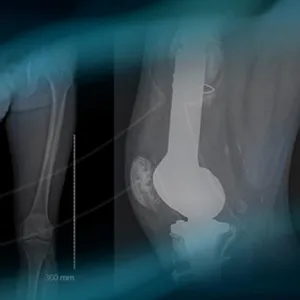

Follow Louis Dagneaux and his team on a revision knee arthroplasty in a patient with segmental metaphyseal tibial bone loss. See how bone allograft is a good option to treat these cases.

What are the different therapeutic options in case of fracture in a massive reconstruction knee prosthesis?